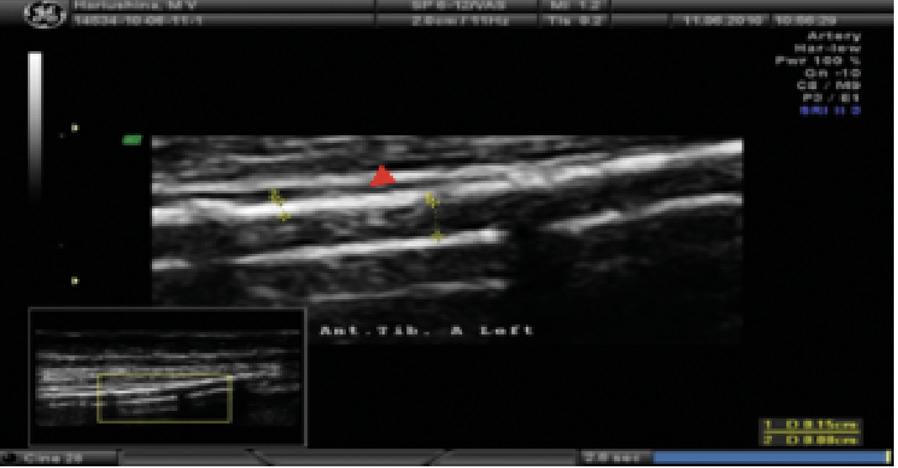

При ультразвуковом дуплексном сканировании артерий нижних конечностей в 2022 г. выявлен атеросклероз магистральных артерий нижних конечностей, эхографические признаки выраженного кальциноза магистральных артерий (рис. 4), окклюзирующий хронический тромбоз левой задней большеберцовой артерии в верхней и средней трети голени.

Рис. 4. Эхограмма пациента Т. Левая передняя большеберцовая артерия. Визуализируется диффузное относительно равномерное повышение эхогенности сосудистой стенки в сочетании с утратой дифференцировки на слои на всем протяжении (красная стрелка). Эхографические тени от повышенного содержания солей кальция фрагментарно перекрывают просвет и нижнюю стенку сосуда (желтые стрелки)